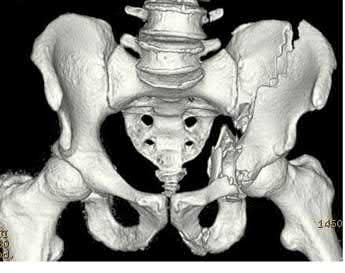

A 35-year-old patient is involved in a motor vehicle collision and sustains multiple injuries, including an APC pelvis fracture. He is stabilized following placement of a pelvic binder and receiving blood products as part of a massive transfusion protocol. He is subsequently taken to radiology for radiographs and a chest, abdomen, and pelvis CT with 4mm cuts. What effect will these modalities have on the radiographic appearance of his pelvis fracture and what further intervention should be performed?

Application of a pelvic binder and CT scans prior to standard AP pelvis radiographs results in an underestimation of pelvic ring injury severity. Since this patient was hemodynamically unstable and required a massive transfusion,

removal of the pelvic binder is not recommended and further injury stability should be evaluated by fluoroscopic examination under anesthesia.

Pelvic ring fractures are high energy injuries that usually follow motor vehicle collisions. There is a high rate of hemodynamic instability with these injuries due to the increase in pelvic volume and abundant venous bleeding. Proper identification of injury severity in the initial evaluation is crucial to ensure appropriate definitive treatment. Ideally, if the patient is hemodynamically stable, AP pelvis radiographs without a pelvic binder have been found to be effective at identifying unstable pelvic injuries.

Fagg et al. performed a retrospective study of 97 patients presenting with pelvic ring fractures requiring operative stabilization. The authors found that 7% of patients that initially had binder-on imaging were found to have unstable fractures that were not identified on the original images. The authors suggested that pelvic CT scans with the binder on are insufficient in determining the severity of pelvic fractures.

Swartz et al. performed a retrospective study of 43 patients presenting with pelvic ring fractures that received AP pelvic radiographs, pelvic binder, pelvic CT, and fluoroscopic stress examination in sequential order. They found that pre-binder radiographs had a greater sensitivity at detecting unstable fractures than pelvic CT with a binder. The authors concluded that placement of a binder prior to imaging can underestimate the severity of the pelvic injury and in cases where a binder is placed prior to imaging a fluoroscopic examination under anesthesia can be useful in detection.

Gibson et al. performed a retrospective review of 72 patients that presented with pubic diastasis requiring internal fixation. The authors found that pelvic CT scans without a pelvic binder underestimated the diastasis by 6.6mm compared to AP pelvic radiographs. The authors recommend obtaining radiographs prior to performing a CT, as underestimation of pubic diastasis can alter definitive management decisions.